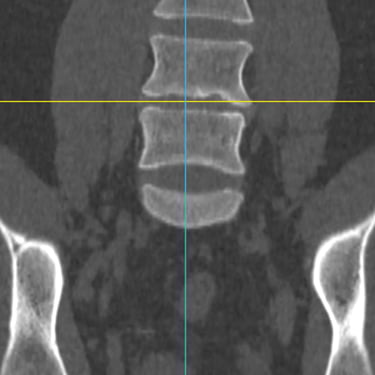

El síndrome postdiscectomía se presenta cuando persiste o reaparece el dolor lumbar y radicular después de una cirugía previa de hernia discal. Puede estar asociado a inestabilidad segmentaria, fibrosis epidural o degeneración discal progresiva. Cuando el manejo conservador no logra aliviar los síntomas, la fusión intersomática transforaminal (TLIF) mínimamente invasiva constituye una alternativa eficaz. Este procedimiento permite descomprimir las estructuras nerviosas, restaurar la altura discal y estabilizar el segmento afectado con menor daño muscular. La técnica mínimamente invasiva favorece menor sangrado, recuperación más rápida y mejores resultados funcionales.